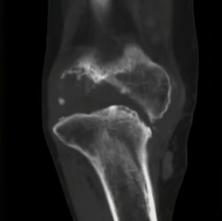

痛风性关节炎骨缺损

但是很多痛风性关节炎的病人就诊时,已经严重到无法行走。他们多数已经发生关节侵蚀,也就是结晶石导致关节的畸形,骨缺损,使得膝关节的力线改变,出现关节内外翻的情况。

同时因为骨缺损,在原有关节置换步骤中,要进行植骨。对于比较复杂的病例,可以通过术前3D扫描获取解剖及结构学数据,定制符合缺口大小的骨植入物,将原本缺损的部分,填充起来,以增加人工关节的稳定性,延长使用寿命。